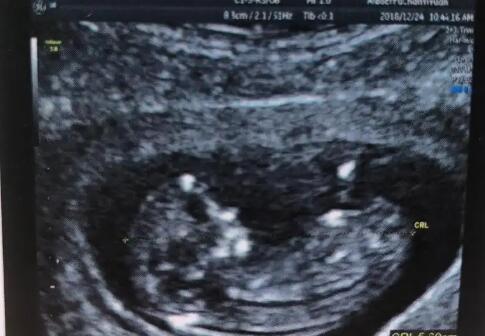

邯郸试管多少钱 2023 邯郸妇幼保健院试管婴儿成功率: ‘b超查女孩儿准确率高

2022邯郸妇幼保健院试管婴儿成功率:

邯郸市妇幼保健院生殖中心试管婴儿成功率在40%-51%左右,妊娠率在40%以上。生殖中心建立了辅助生殖实验室和胚胎培养室,严格按照卫生部关于辅助生殖技术的规范要求。近年来,医院生殖中心的试管婴儿周期逐年增加,保持了较高的成功率。以下依据1颗基础卵泡数量预测到邯郸妇幼保健院做试管成功率,可参考下表: